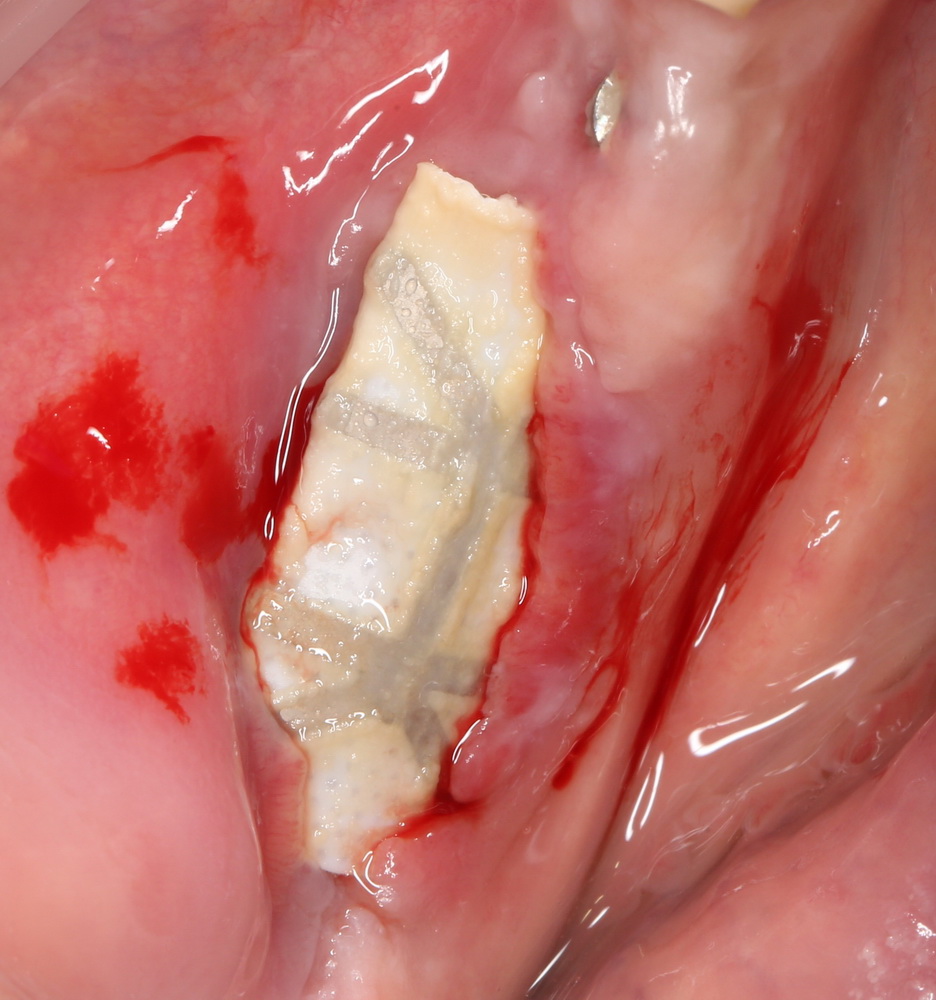

Сначала фиксируется BioGide. Это легко:

Если после этого BioGide намочить физраствором, им легко укрыть получившийся объем:

Для надежности можно зафиксировать пинами: